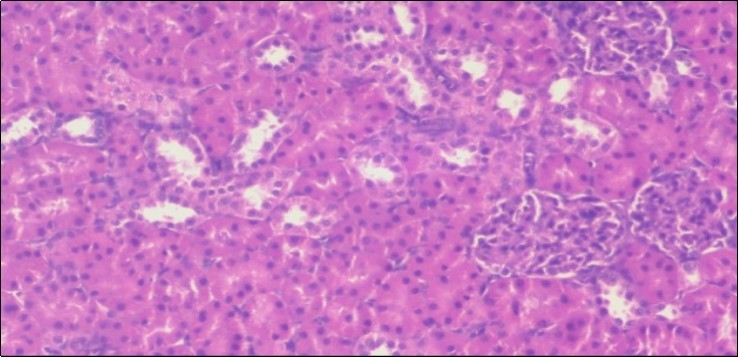

Effect of Ator, Fennel and Their Combination on the Liver of Obese Rats

The histological examination of the livers of control rats feeding standard diet showed normal architecture hepatocytes, blood sinusoid and central vein, figure 6. The rats which were fed on a (HFD), showed swollen hepatocytes with vacuolated cytoplasm filled with fatty infiltration, congested central vein and disappearance of blood sinusoids, figure 7. By comparison, the liver of rats that were treated by fennel after obesity and control mice observed nearly normal of the hepatocytes with eosinophilic cytoplasm, central vein and clear blood sinusoids and more bi-nucleated cells, figure 8. While examination of rats' liver that were treated by Ator and after the obesity appears, they showed mild fatty change in hepatocytes, few hepatocytes retain is eosinophilic cytoplasm and central vein figure 9. Liver of rats that were treated by fennel and Ator after obesity and control rats are showing nearly normal hepatocytes figure 10.

Figure 6.Photomicrogragh of liver section of control rat showing normal architecture Hepatocytes, blood sinusoid and central vein, (H&E) (40X).

Figure 7.Photomicrograph of liver section of obese rat showing swollen hepatocytes with vacuolated cytoplasm filled with fatty infiltration, congested central vein and disappearance of blood sinusoids, (H&E) (40X).